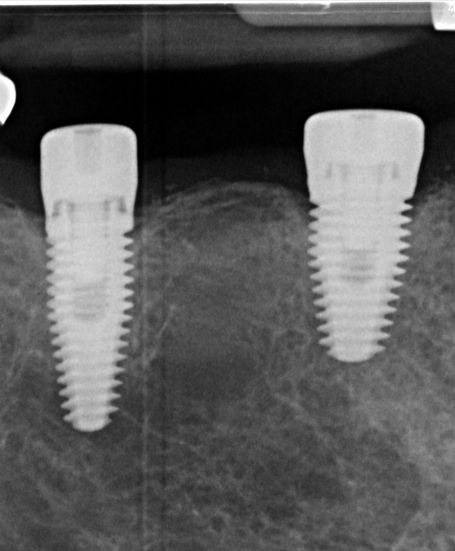

Dental implants are a reliable solution for replacing missing teeth. Unlike dentures or bridges, implants use a titanium screw that integrates with your jawbone, acting as a stable foundation that mimicks a tooth's root for a custom-made crown. This approach ensures your new tooth looks, feels, and functions with a natural and comfortable feel.

Implant Placement: The titanium screw is gently placed into your jawbone. Over time, it integrates with the bone, creating a strong foundation. We usually give the implant 3 months to heal into your bone. Everyone is different, that is why this might differ for you.

• Restoration: Once the implant is secure, a healing abutment is placed to reshape the gums to a create the right environment for the future porcelain crown. Once the gums have healed, a custom crown is attached, completing your smile.